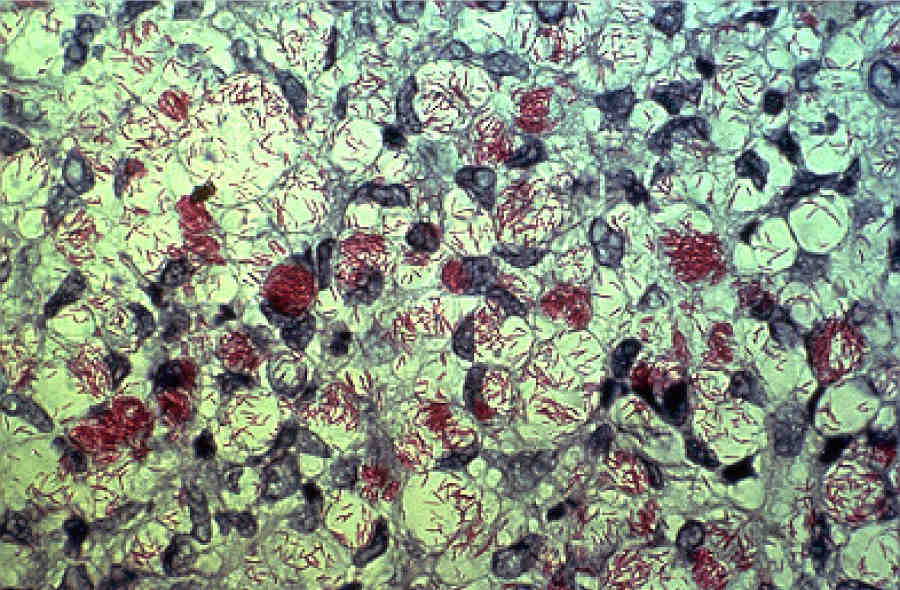

Возбудитель лепры, Mycobacterium leprae, является одним из первых идентифицированных микробных патогенов человека. Однако, несмотря на давнее открытие, сделанное Г.А. Хансеном в 1873 г., бактерия до сих пор не была культивирована in vitro.

Принадлежность возбудителя к микробактериям была установлена на основании кислотоустойчивости, морфологии, а также вызываемых им гранулематозных поражений.

Бактериологические исследования M. leprae начали проводить только в 60-е гг. XX века, после того как Шепард сообщил о возможности выращивания бактерий в подушечках лап мышей. А получать микробный антиген в большом количестве начали тогда, когда в качестве модельных объектов для культивирования инфекционного агента стали использовать броненосцев.